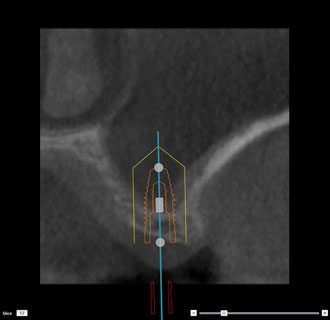

インプラント シュミレーション画像1

インプラント治療や、埋もれている歯の抜歯、口腔内の手術などを行う場合には、まずコンピューターでシミュレーションを行います。

CT画像をノーベルクリニシャン®︎で処理することで、様々な角度から画像を分析することが可能です。ノーベルクリニシャン®︎を使用する事で、より安全な治療が可能となりました。